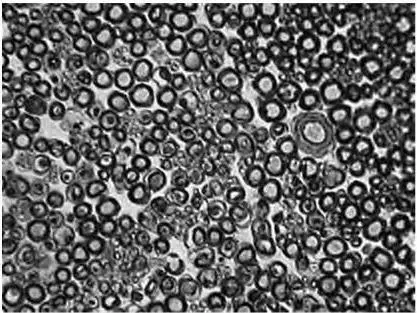

Рис. 1.4 . Поперечный срез периферического нерва

Эндоневрий также состоит из клеточного и волокнистого компонентов. Частью его являются уплощенные клетки, начинающиеся от внутреннего слоя периневрия и разделяющие ствол в виде перепончатых перегородок на множество отдельных пучков нервных волокон. Эти клетки снабжены отростками и тесно связаны между собой. В эндоневрии встречаются редкие фибробласты веретеновидной формы, прилежащие, иногда вплотную, к миелиновым волокнам, а также тучные клетки.